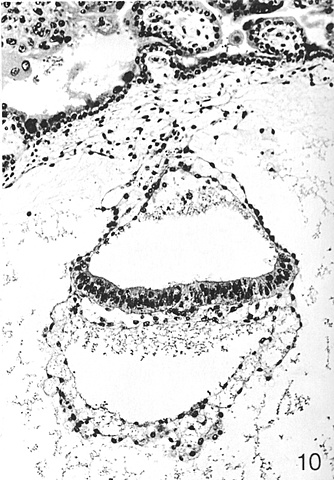

• Day 7- Secretory Phase (Stage 5)

Day 7- Secretory Phase (Stage 5)

During stage five, implantation is completed. The trophoblast cells proliferate and the maturnal endometrium begins the decidual process and the endometrial stroma accumulates fluid. The extraembryonic cavities also begin to form and the bilaminar embryonic disc forms from the inner cell mass.